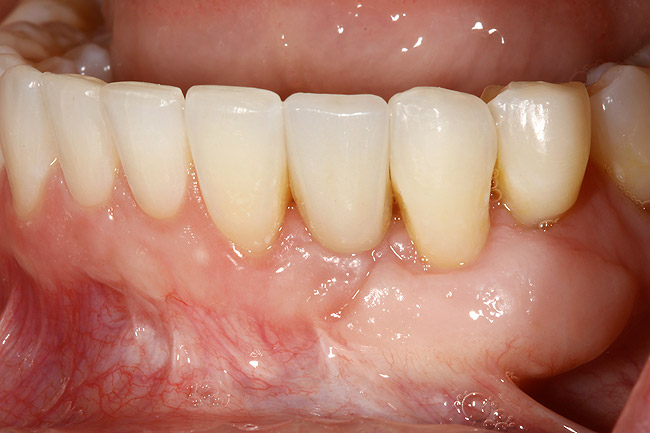

Figure 8  Adequate keratinized and attached gingiva after free gingival graft surgery.

Figure 8

This treatment plan was elected with the premise to reevaluate treatment options during orthodontic tooth movement. Soft-tissue augmentation was initiated to correct the mucogingival defect in the area of teeth Nos. 21 and 22. A free gingival graft was performed to achieve an adequate band of attached and keratinized gingiva to resist potential stripping on the root surfaces of teeth Nos. 22 and 21 during orthodontic movement (Figure 8). Orthodontic movement then was initiated to site-develop position No. 23 for an implant (Figure 9 through Figure 11). Orthodontics also was used to idealize the patient’s occlusion and develop canine guidance to minimize occlusal load and maximize the redistribution of forces36-40 for protecting the future implant from deleterious forces. The space was opened around the peg lateral tooth No. 7, and the gingival levels were aligned for maxillary incisors. Bonding was performed to restore the length of teeth Nos. 8 through 10 and to bond the peg lateral to a normal tooth form, which allows the orthodontist to idealize the posterior occlusal scene and maintain canine guidance (Figure 12 through Figure 13).